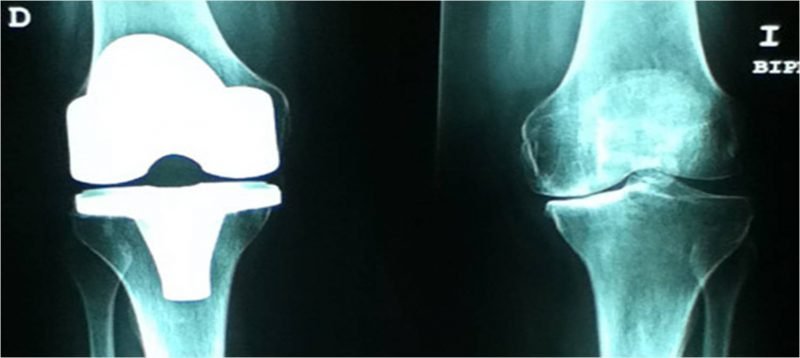

En qué Casos Utilizar Prótesis en Rodilla: Cuando existen daños severos en las rodillas, se tiende a hacer una cirugía en la que se inserta una prótesis total de rodilla. Esta nueva rodilla es de materiales espaciales que aliviarán el dolor y harán que se mantenga la función de la misma para el paciente.

Las prótesis de rodilla tienen una duración de entre 25 y 35 años; pero no durará más de ese lapso, puesto que como todo material, va a irse desgastando y aflojando. Por esta razón, una vez que pase dicho tiempo, comenzarán a sentirse los síntomas de aflojamiento. A los pacientes jóvenes no se los ponen porque en algún momento de su vida tendrán que hacer un cambio de prótesis.